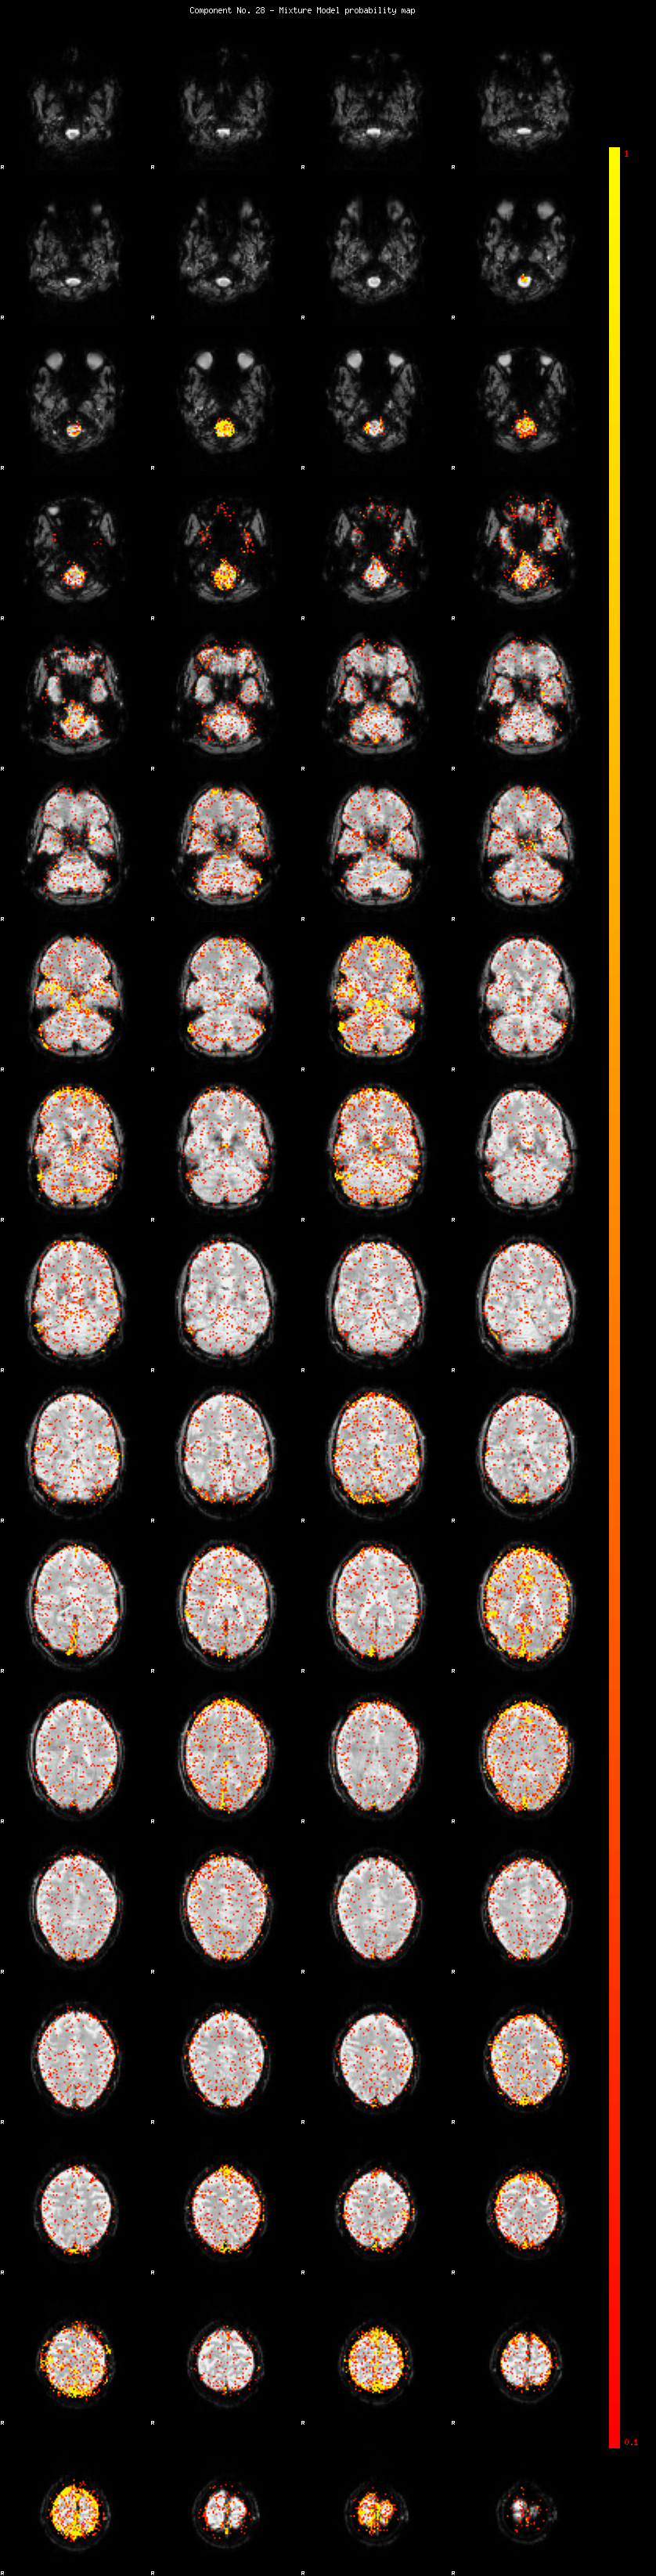

IC_28 Mixture Model fit

Means : -0.000000 2.930921 -2.556320

Vars : 1.000000 3.653941 2.269429

Prop. : 0.925134 0.038218 0.036648